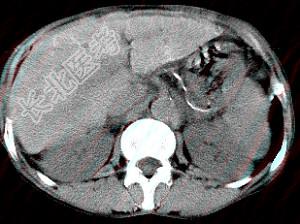

- 单项选择题男,40岁有血吸虫感染史,腹胀不适,食欲减退,CT扫描所见如图,最可能的诊断是 ( )

A、肝炎后肝硬化

B、血吸虫后肝硬化

C、酒精性肝硬化

D、胆汁性肝硬化

E、脂肪肝